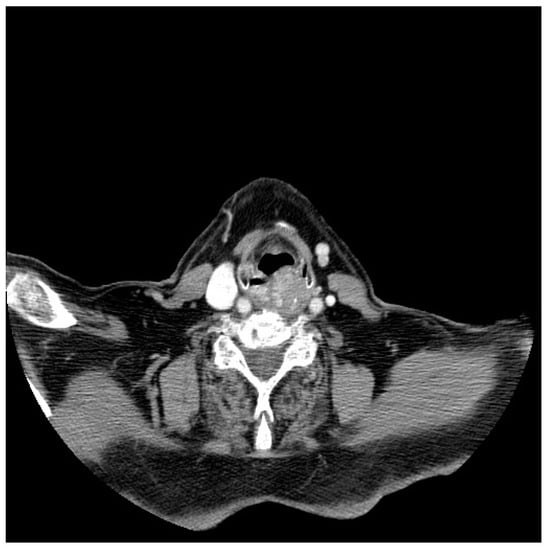

3.1. Diagnostic Workup

- Doğan, S.; Vural, A.; Kahriman, G.; İmamoğlu, H.; Abdülrezzak, U.; Öztürk, M. Non-squamous cell carcinoma diseases of the larynx: Clinical and imaging findings. Braz. J. Otorhinolaryngol. 2020, 86, 468–482. [Google Scholar] [CrossRef]

- Banko, B.; Đukić, V.; Milovanovic, J.; Kovač, J.; Artiko, V.; Maksimović, R. Diagnostic significance of magnetic resonance imaging in preoperative evaluation of patients with laryngeal tumors. Eur. Arch. Oto-Rhino-Laryngol. 2011, 268, 1617–1623. [Google Scholar] [CrossRef]